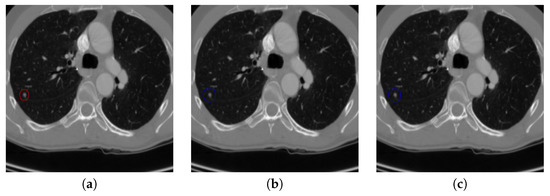

Figure 9.

An example of detecting nodule candidates from the chest CT image. (a) is the input chest CT image, (b) is the nodule candidates detected by the proposed nodule candidate detection sub-network, (c) is the ground truth nodule region.